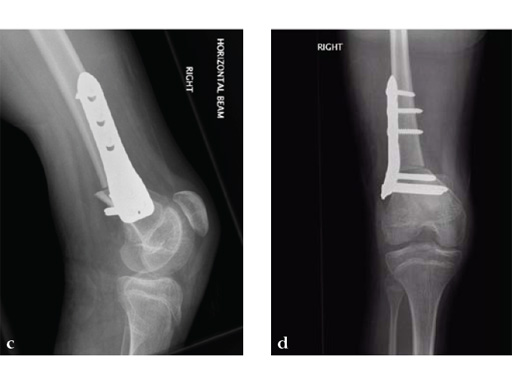

A 12-year-old girl presented for the first time to the cerebral palsy clinic. Although weak as well as spastic she was able to stand and step and wished to walk better. Physical examination revealed fixed flexion deformity of both knees. Distal femoral osteotomy with some shortening was the preferred option as hamstring lengthening and posterior knee capsule release would have caused further weakening.

Osteotomies were stabilized with the 5.0 mm LCP pediatric condylar plate. Postoperative management was non-weight bearing in splints, followed by weight bearing and rehabilitation at 6 weeks. Osteotomies healed uneventfully.